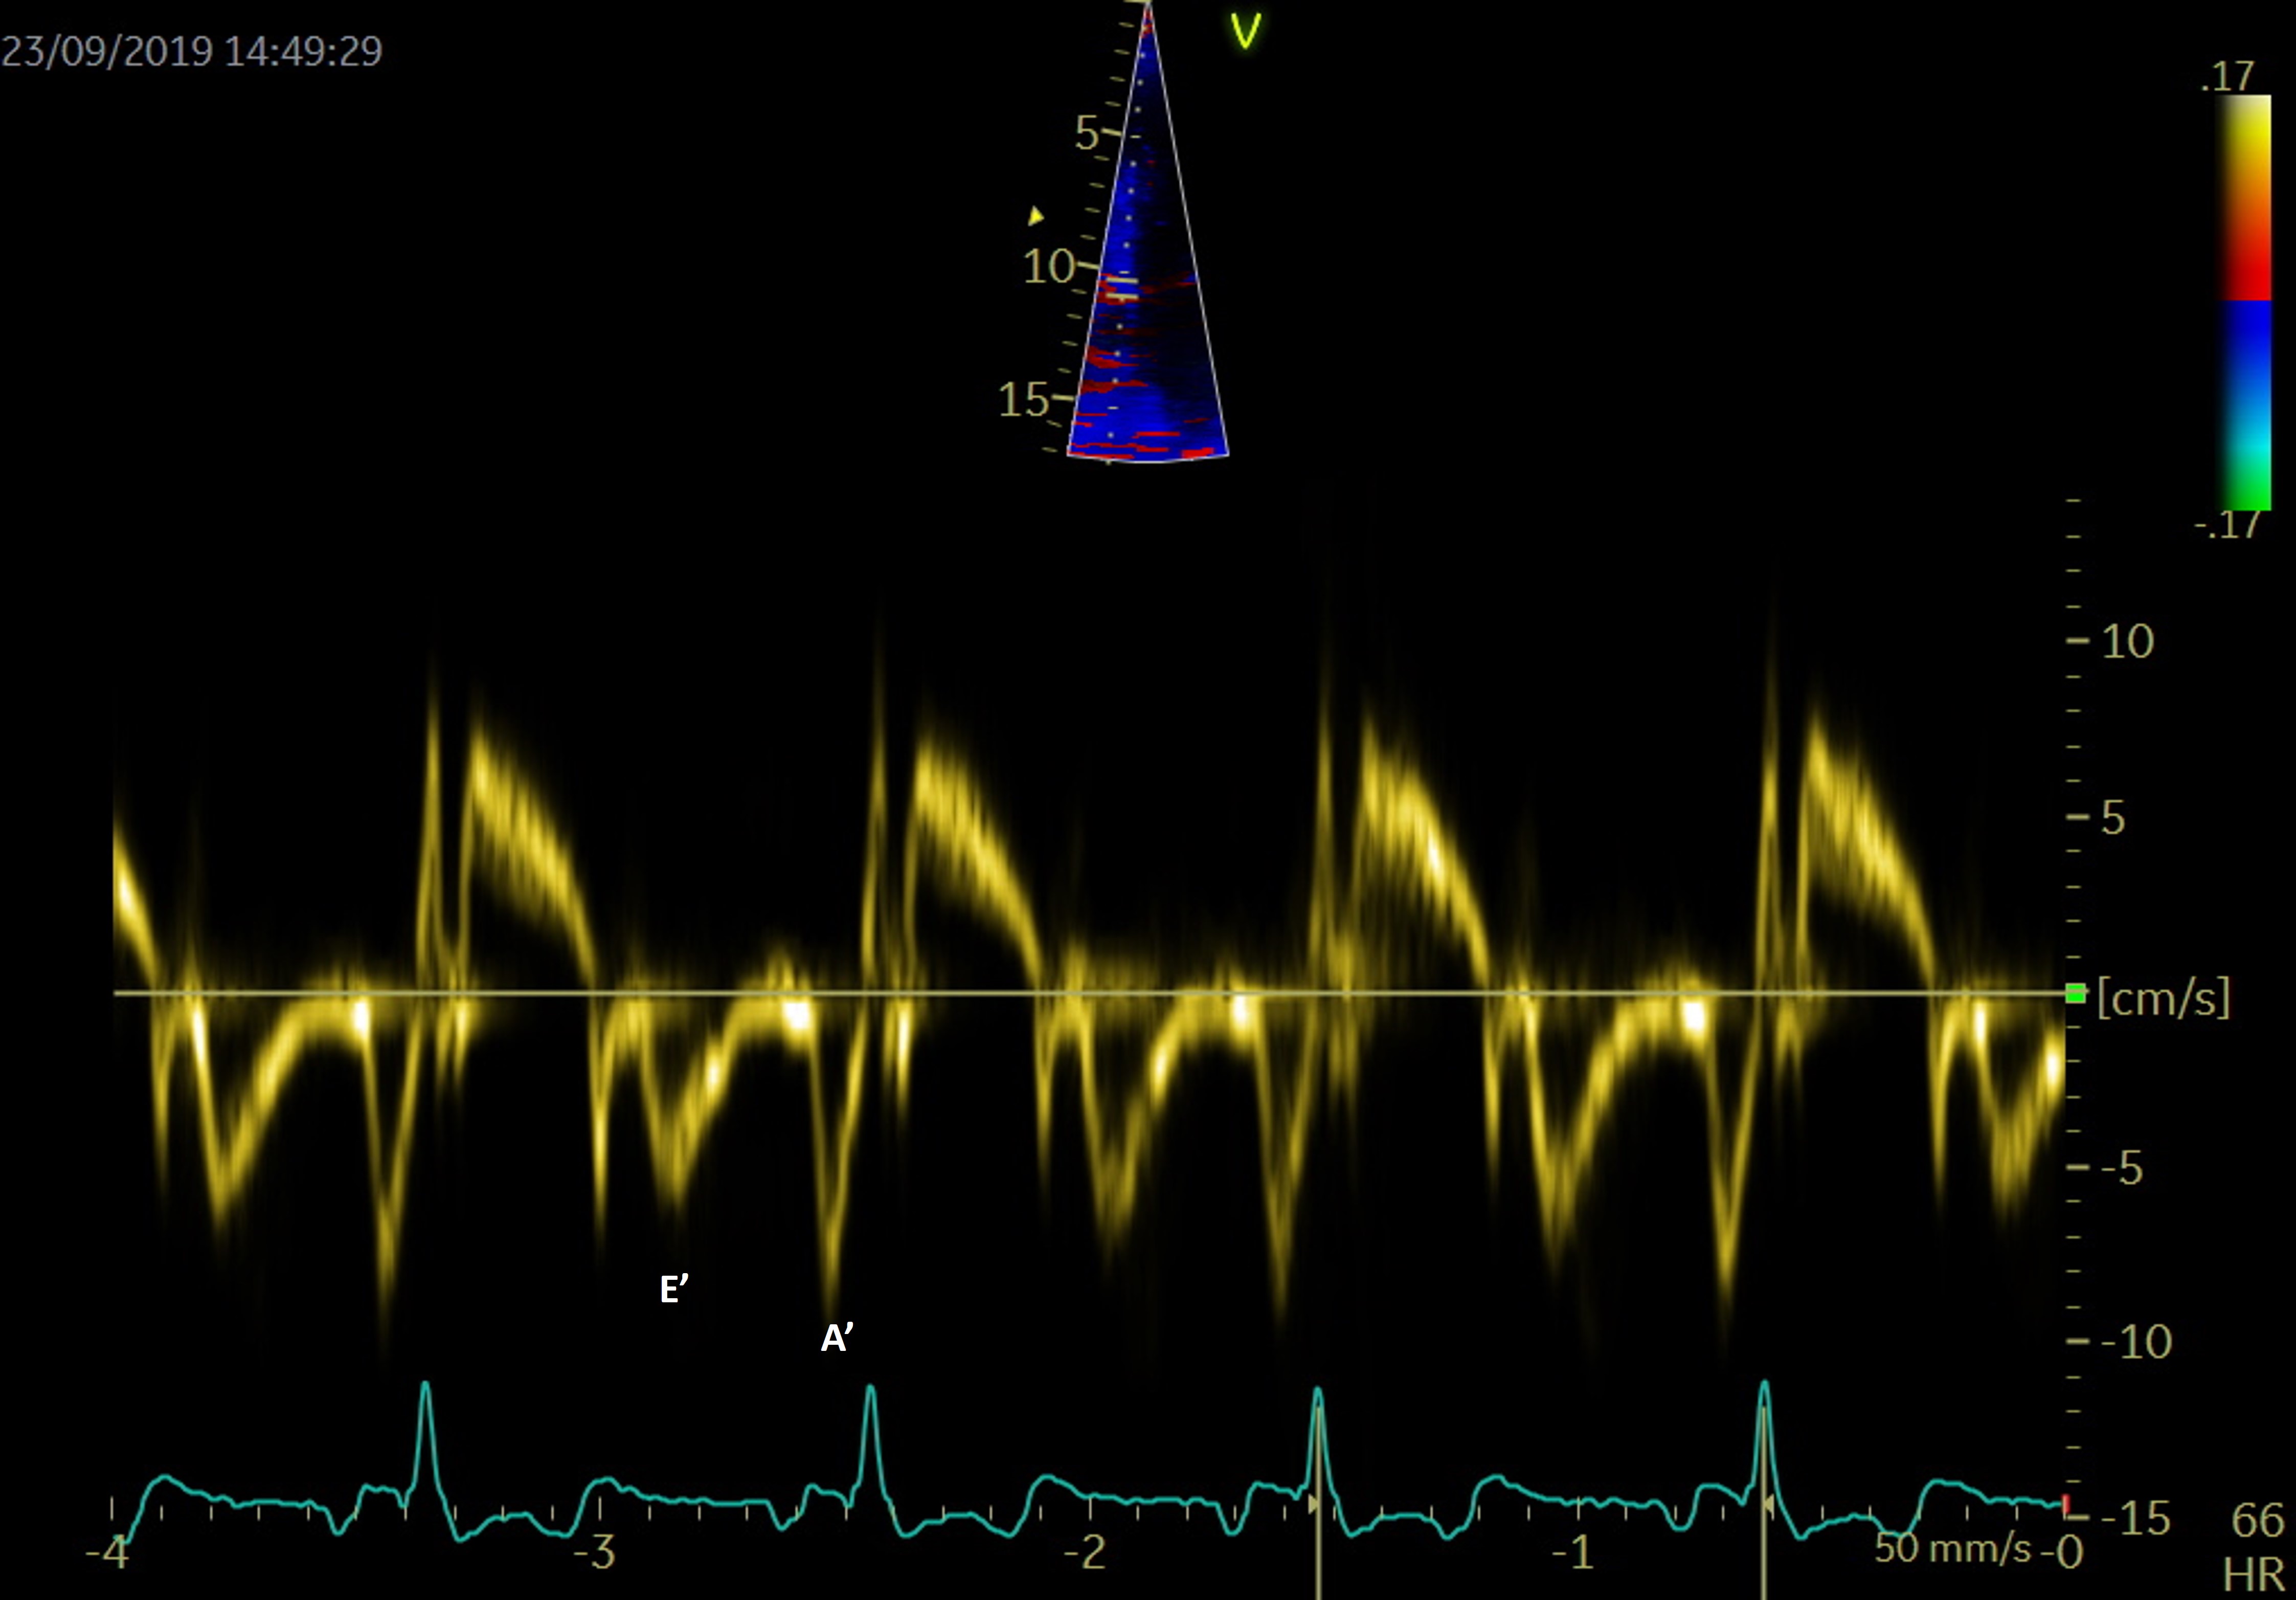

PW tissue Doppler imaging (TDI) is performed in the apical 4-chamber view, with the sample volume placed at the level of the mitral annulus, to evaluate the left ventricular wall motion (Fig. 7). The E/E’ ratio, correlates to LA pressures and is associated with an increased risk of late AF recurrence after catheter ablation. The risk is 3.32 times higher for a threshold over 13.25 [75].

Fig. 7.

Fig. 7.PW Tissue Doppler evaluation at the level of the septal mitral annulus for evaluation of E’ and A’.

TDI can also assess an atrial segment of interest, and measurements are usually done at the lateral wall level. The peak velocity in late diastole correlates to atrial contraction (A’) and is a rapid and accurate marker of atrial function. Hesse et al. [76] demonstrated a good correlation between A’ and LA fractional area and volume change in quantifying LA systolic function.

In AF patients there is a decreased compliance of LA walls, as during AF the reservoir and conduit function are impaired, and the booster pump function is lost. The S wave corresponds to the reservoir function, the lateral atrial E’ wave to the blood conduit, and the atrial A’ wave to the atrial contraction function.

The LA activity closely relies on the left ventricle functional parameters, and changes in left ventricle function and left atrial mechanics are independent and interrelated. Diastolic dysfunction and AF have many common risk factors, including aging [77]. It is known that most diastolic parameters vary with age: E and E’ wave velocities decrease, while the A wave, the E wave deceleration time and E/E’ ratio increase depending on age [78].

Not only the presence, but also the severity of left ventricle diastolic dysfunction is independently predictive of newly developed AF [79]. Early diastole filling evaluated by tissue Doppler mitral annulus motion velocity (the E’ wave) is reduced in patients with diastolic impairment. In this context, the E/E’ ratio evaluates filling pressures of the LA and left ventricle stiffness. In patients with diastolic dysfunction, the E/E’ ratio is used as an independent predictor of AF [80]. The relationship between transmitral E velocity (related to LA pressure and left ventricle relaxation) and tissue Doppler mitral annulus velocity (E’ – reflects left ventricle relaxation) reflects atrial pressures, irrespective of left ventricular function. This ratio seems to have a clinical relevance in risk stratification in patients with AF. A ratio over 11.2 was determined as a predictor for early AF recurrences [55], while a higher ratio, over 13.25, was established as an independent predictor for late AF recurrences [75]. A septal E/E’ ratio over 15 was evaluated as an independent predictor of mortality in patients with AF [81]. Both lateral atrial E’ and the ratio E’/A’ show a good correlation with various diastolic dysfunction parameters and LA strain [82]. While E/E’ ratio has been validated as an independent predictor of evolution and recurrences in the evaluation of outcome in patients with AF, data regarding thresholds are still missing [37, 55].

Atrial electromechanical delay or LA dyssynchrony time can also be measured by TDI. It is a feasible method that can evaluate the presence and extent of LA remodeling in addition to conventional echocardiographic parameters. TDI PA peak time (PA peak - TDI) is defined as the time measured from the start of the P wave in lead II to the peak of A wave on the tissue Doppler tracing from the lateral LA wall. Left atrial asynchrony was demonstrated to be an independent predictor for AF recurrence after radiofrequency ablation [83].

Tissue imaging is mostly used in clinical practice to determine the E/E’ ratio, as this parameter gives information about the relation between the LA and the left ventricle.